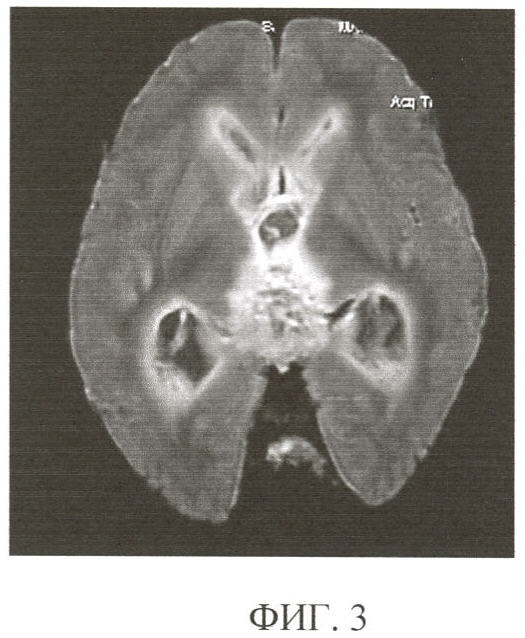

Пример 1. Пациенту (И.б. 1812-05, РНХИ) 19 лет была произведена трепанация черепа по поводу герминомы области шишковидной железы. В послеоперационном периоде течение заболевания осложнилось присоединением гнойных инфекций и развитием гидроцефалии. Несмотря на проводимое интенсивное лечение больной скончался с явлениями нарастания очаговой и общемозговой симптоматики, причина которых не была до конца ясна. Согласно заявляемому способу при МРТ с импульсной последовательностью Inversion Recovery (фиг.3) абсолютно идентично макропрепарату определяется опухолевый узел, расширенная желудочковая система, внутрижелудочковые наложения, обусловленные наличием вентрикулита. Кроме того, посмертная МРТ выявляет перивентрикулярное свечение, в то время как субэпендимальные отделы белого вещества на макропрепарате выглядят неизмененными (фиг.4). Прицельное гистологическое исследование зон гиперинтенсивного магнитно-резонансного сигнала в веществе головного мозга вокруг желудочков выявило распространение воспалительного процесса с развитием энцефалита с обильной лимфоплазмоцитарной инфильтрацией и отечными изменениями белого вещества мозга (фиг.5).